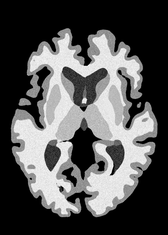

4.2 Registration to a 100 micron ex-vivo brain MRI volume

To showcase the efficacy of our method on real large scale images, we register a 250 in-vivo MRI image (Lüsebrink et al., 2017) to a 100 ex-vivo FLASH human brain volume (Edlow et al., 2019). This represents an inverse problem with more than 11.2B optimizable parameters (compared to 20M for clinical datasets), or 44.8GB of GPU memory. The entire problem does not fit on most GPUs, necessitating distributed multimodal registration. We optimize a composite transform - affine followed by a diffeomorphic mapping; details can be found in Section E.1. Multimodal deformable registration took 58 seconds on 8 NVIDIA A6000 GPUs, which is unprecedented at this resolution. Fig. 6 shows qualitative results, highlighting the ability to register highly detailed structures such as cerebellar white matter; these structures are not visible at macroscopic scales. The resultant advantages of performing registration at this scale can allow researchers to characterize the neuroanatomy at microscopic resolutions and allow morphometric analysis of cortical layers and subcortical nuclei among other structures.